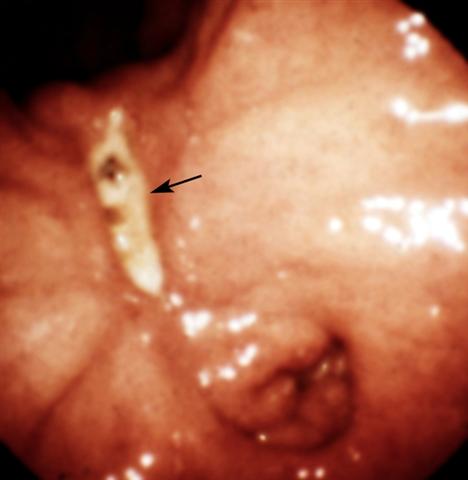

Рис. 8. Эндоскопическая картина желудка в норме и при различных заболеваниях. Язва малой кривизны желудка (указана стрелкой) с тенденцией к рубцеванию: видна конвергенция складок слизистой оболочки к краям язвы.